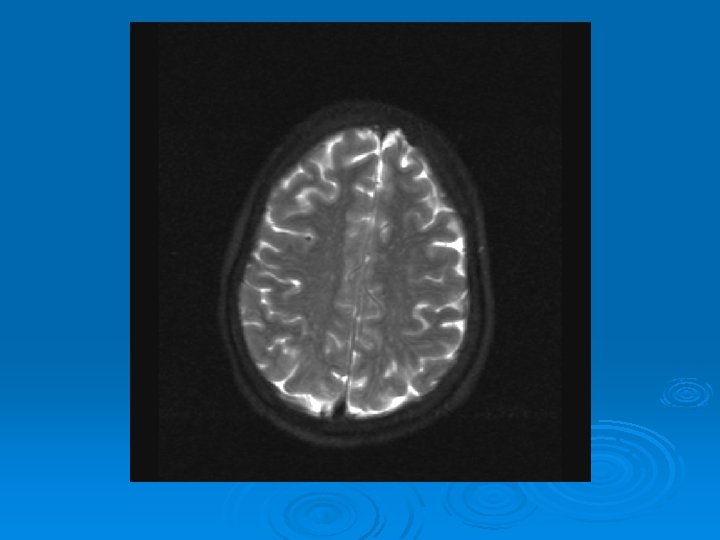

MRI: 2/9/2007 Ø 1. Leptomeningeal enhancement, most prominently seen over the posterior parietal and occipital lobes.